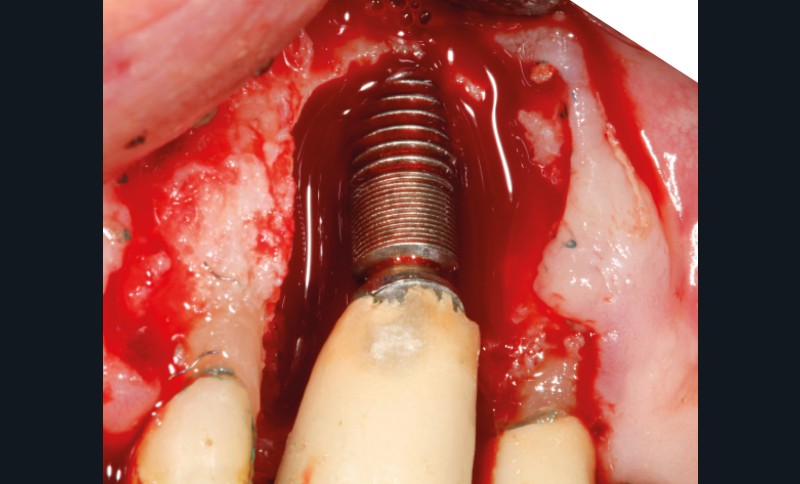

L’implant

- Site 23

- Mis en place il y a 12 ans

– Le laser Er-YAG, utilisé pour le nettoyage, est un laser avec un milieu actif composé d’yttrium, d’aluminium et de grenat dopé à l’erbium. Avec une longueur d’onde de 2 940 nm situé dans l’infrarouge, le laser Er-YAG est un laser à haute énergie, dont la lumière est absorbée dans l’eau et dans l’hydroxyapatite et qui ne pénètre pas profondément. Ceci permet de couper des tissus mous et des tissus durs, mais également de désorganiser le biofilm bactérie.